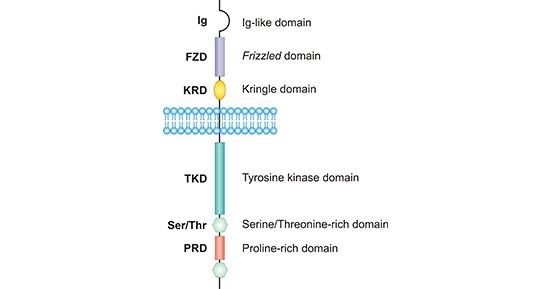

MET(hepatocyte growth factor receptor,HGF receptor)是受體酪氨酸激酶(RTK),它在細胞生長、增殖、分化和遷移等生物學過程中起重要作用。